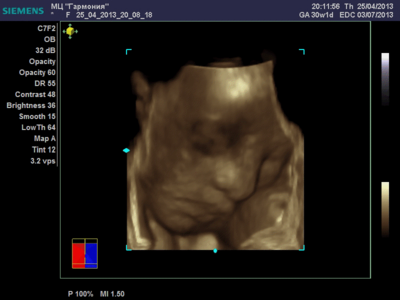

А я вчера на 3Д УЗИ ходила. Моя звезда закрывалась в еми 4мя конечностями. Просто пополам сложилась и спала себе сладко. УЗИстка провела со мной час, кое-как расшевелили маленькую, но ручка была постоянно на мордашке и засыпала она почти сразу снова. Я и на мяче прыгала и живот трясла. В конце более-менее фото вышли, но качество меня не порадовало. Возможно фри оф чардж еще раз переделают. Со средней фотки были отличного качества, а эти сплошное разочарование. Вот тут что-то более-менее еще. Главное пальчик оттопырила так смешно, мол минуточку. Вообще немного жутковатые фотки..хаха

Еще одна, качество ужасное..

ANGEL*ina, у вас качество очень даже неплохое. GE машины очень хорошие. У моей врачихи такая. Мы сегодня ездили на повторное 3Д узи. Повезло немного больше чем неделю назад. У малыша явно шило в попе. Он кувыркался. За 20 минут несколько раз поменял позицию полностью, и под конец вообще отвернулся. Корд тоже постоянно перед его личиком болтался, да и руками он себя частенько закрывал. Качество фотографий ужасней не придумать.

Вот, пожалуй, самая лучшая фотография.

katerina73 писал(а): Вот, пожалуй, самая лучшая фотография. Катюш, так ваш пупсик зато отлично виден, черты лица отменно видны. Те первые две вчерашние, вторые средней дочки. Со средней черты отлично видны, с этой куклой не понятно..